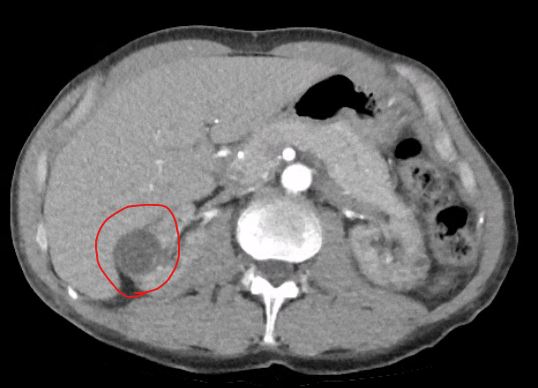

A small renal tumour is noted in the right kidney here. The patient was medically unfit for nephrectomy but still wanted curative treatment.

Three cryoprobes are placed into the lesion using CT guidance and the ice ball is seen to completely cover the lesion.

The procedure was performed with local anaesthesia only and patient discharged home same day.